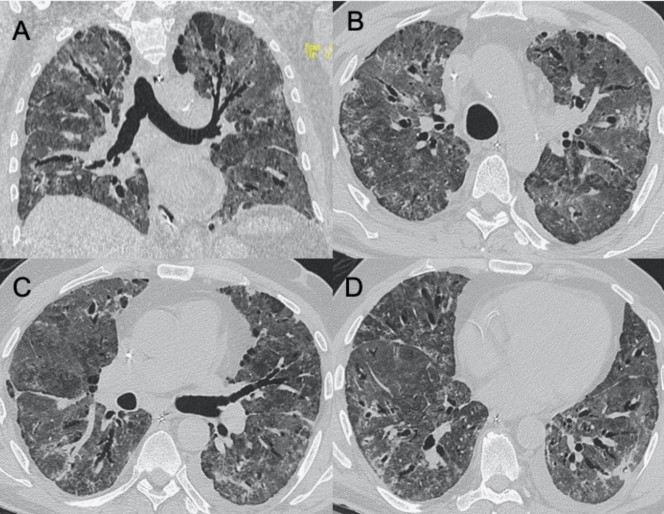

● CT:早期主要為外周、雙側磨玻璃影(ground-glass opacities,GGO),伴實變、小葉間隔和小葉內間隔增厚,形成“鋪路石征”模式??諝庵夤苷?、血管擴大、暈輪征和反暈征也有報告(圖2)。

圖2 COVID-19的HRCT。急性期,雙肺(A)彌漫性GGO,小葉周圍型(B)。圖(C,D)顯示2例亞急性間質性肺炎,GGO減少,存在胸膜下局灶性實變和小葉間/小葉內間質增厚。